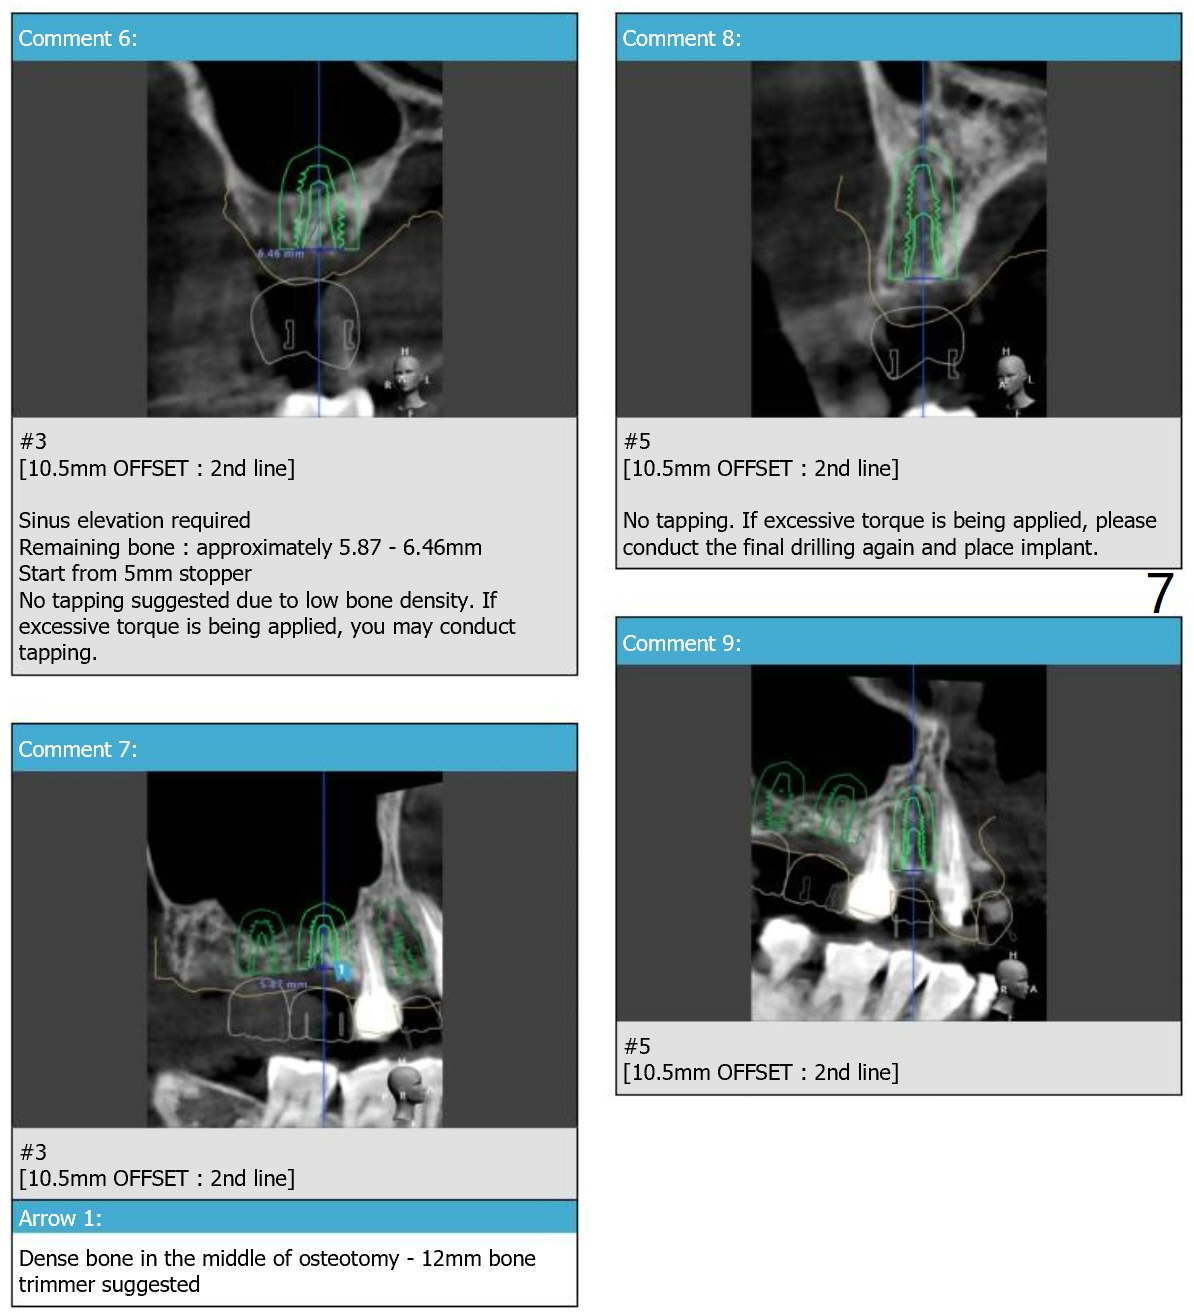

UR 4 Implant Placement with Guide

This case requires both narrow and regular navi guide kits and DIO 1-piece implant kit as well as DIO Sinus kits (regular and guided).